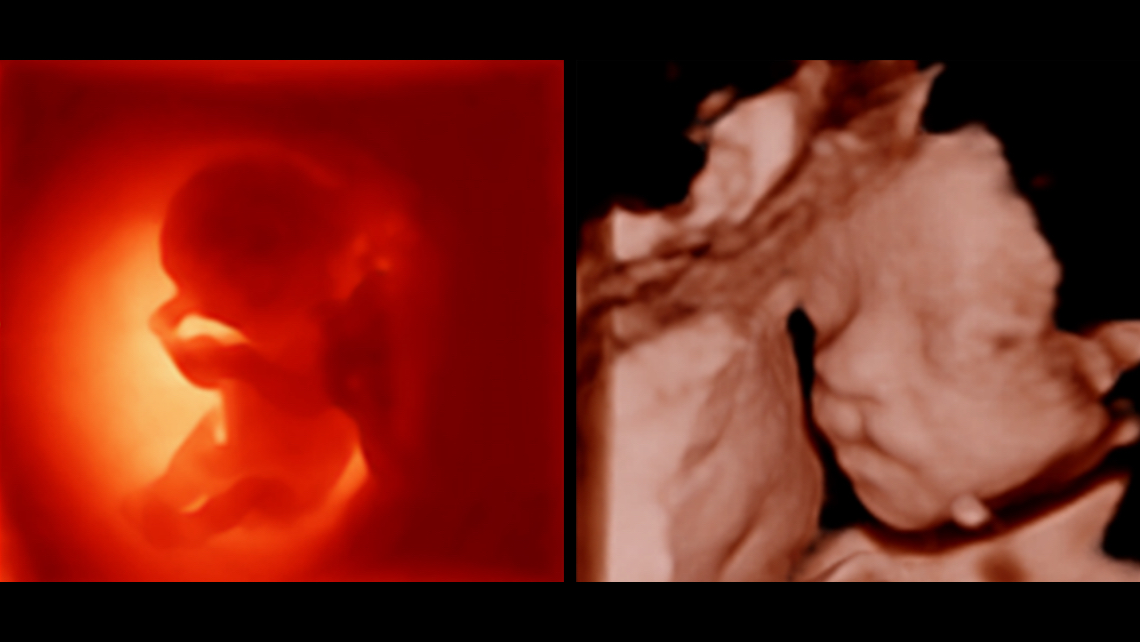

Obrazy kliniczne